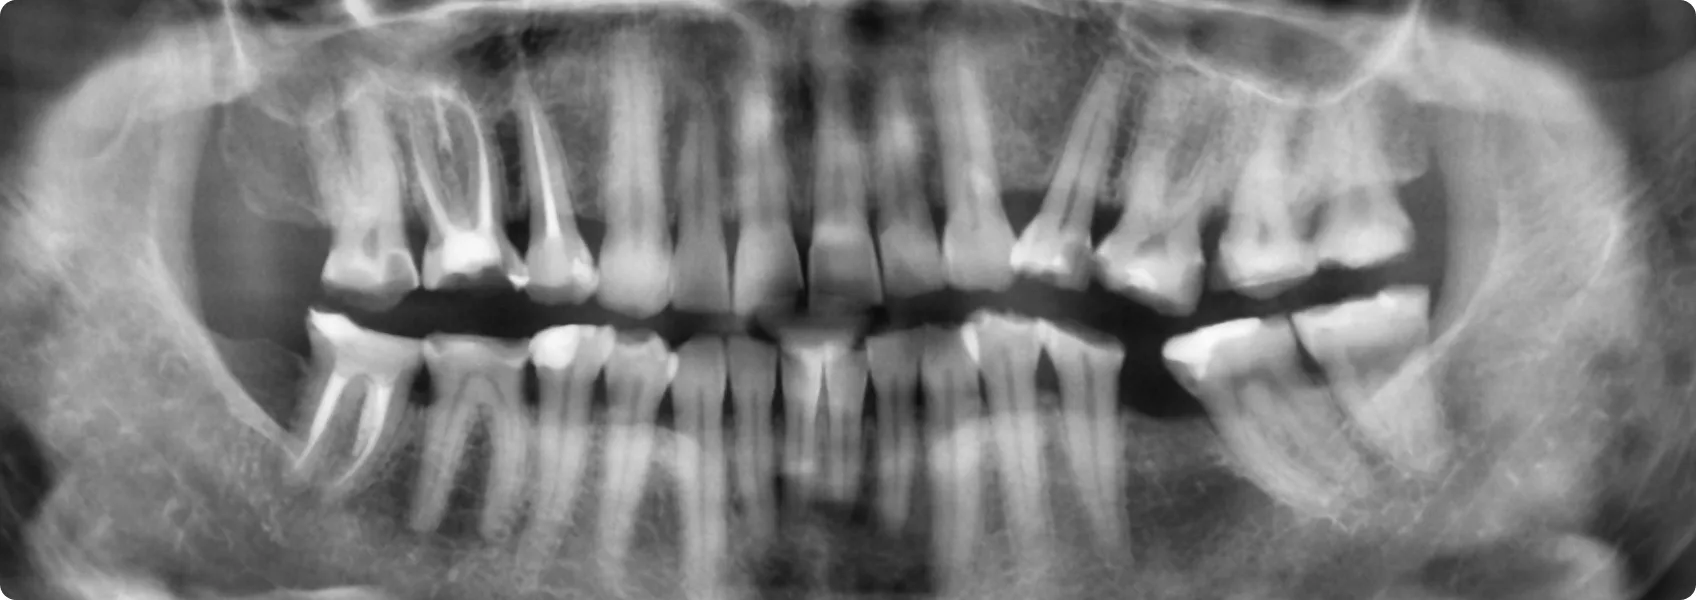

Zaczęliśmy od diagnostyki. Zdjęcia RTG pozwoliły ocenić stan korzeni zębów i kości.

Starty ząb często ma odsłoniętą lub podrażnioną miazgę zębową. RTG pokazuje, czy nastąpiło już zapalenie miazgi, martwica lub inne zmiany wymagające leczenia kanałowego (endodoncji) przed leczeniem protetycznym. Na szczęście, w tym przypadku mogliśmy przystąpić od razu do protetyki.